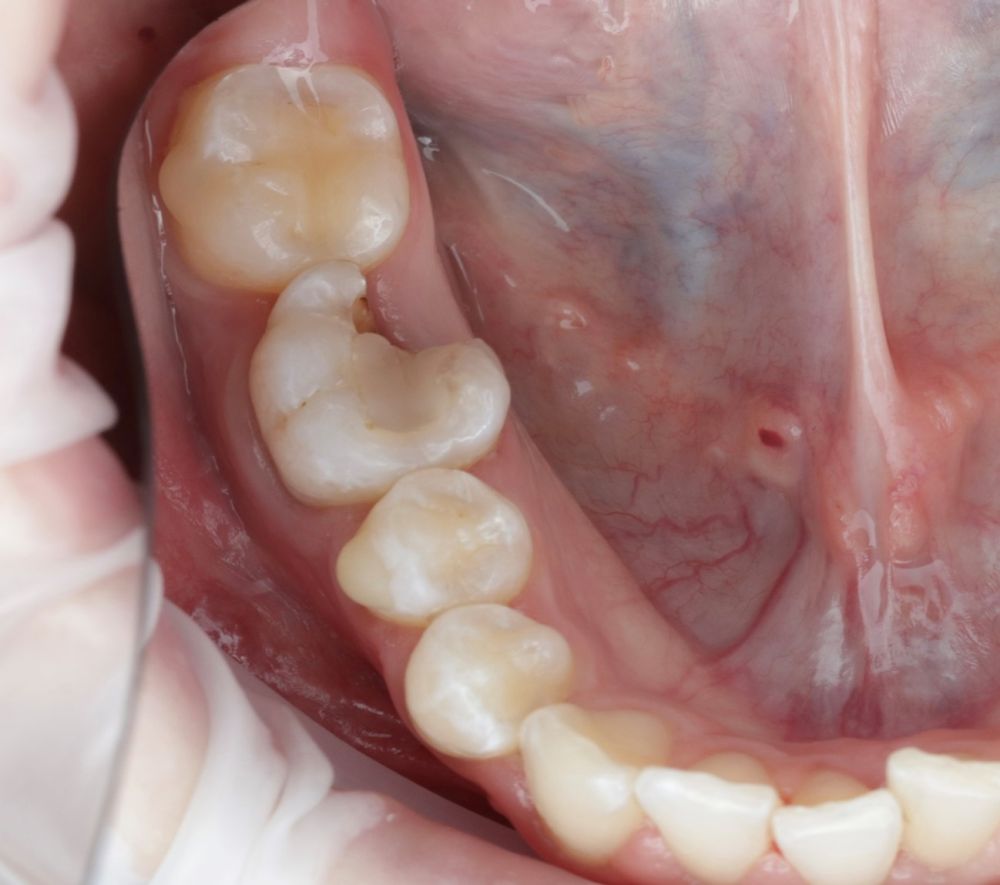

El autotrasplante dental es una opción terapéutica para aquellos casos en la que una pérdida dentaria es reemplazada por un diente donante del mismo paciente. Este autotransplante colocado en el alveolo puede ser inmediato o diferido. Suele estar indicado en paciente joven, siendo más frecuente el autotransplante de cordal a primer o segundo molar, y el de premolar a incisivo. El diente donante debe reunir unos criterios clínicos que aumenten el éxito de la técnica, basados en la morfología, el estadio de desarrollo radicular y la salud periodontal. La planificación se llevará a cabo con un CBCT y simulación virtual que genere un prototipo réplica en 3D; esto permite evaluar las dimensiones del diente donante para su correcta colocación en el alveolo receptor.

Se reporta el caso de un autotrasplante del tercer molar inferior derecho al alveolo postextracción de un primer molar inferior, en una paciente de 22 años de edad. Actualmente, el autotransplante se considera una opción de tratamiento si se siguen los criterios de selección del caso adecuados, y se realiza una técnica quirúrgica protocolizada. El diagnóstico planificado mediante CBCT, la simulación virtual y la confección de una réplica en 3D optimiza la técnica de forma segura, predecible con tiempos de cirugía menores.

Los dientes utilizados para realizar un AD más frecuentemente suelen ser de premolares a incisivo, de cordal a primer o segundo en pacientes jóvenes con ápice abierto. En adultos con ápice cerrado suele ser el autotransplante de cordal a primer o segundo molar3,4,6.

El diente donante ideal debería tener una anatomía radicular de fácil instrumentación endodóntica, y ápice abierto de al menos 1,5mm de diámetro para permitir una adecuada revascularización, con formación radicular de al menos 2/3. Así mismo, debería ser lo suficientemente pequeño para el asentamiento adecuado en el alveolo receptor, cónico, cuya extracción se pueda realizar de forma atraumática3,5,7.